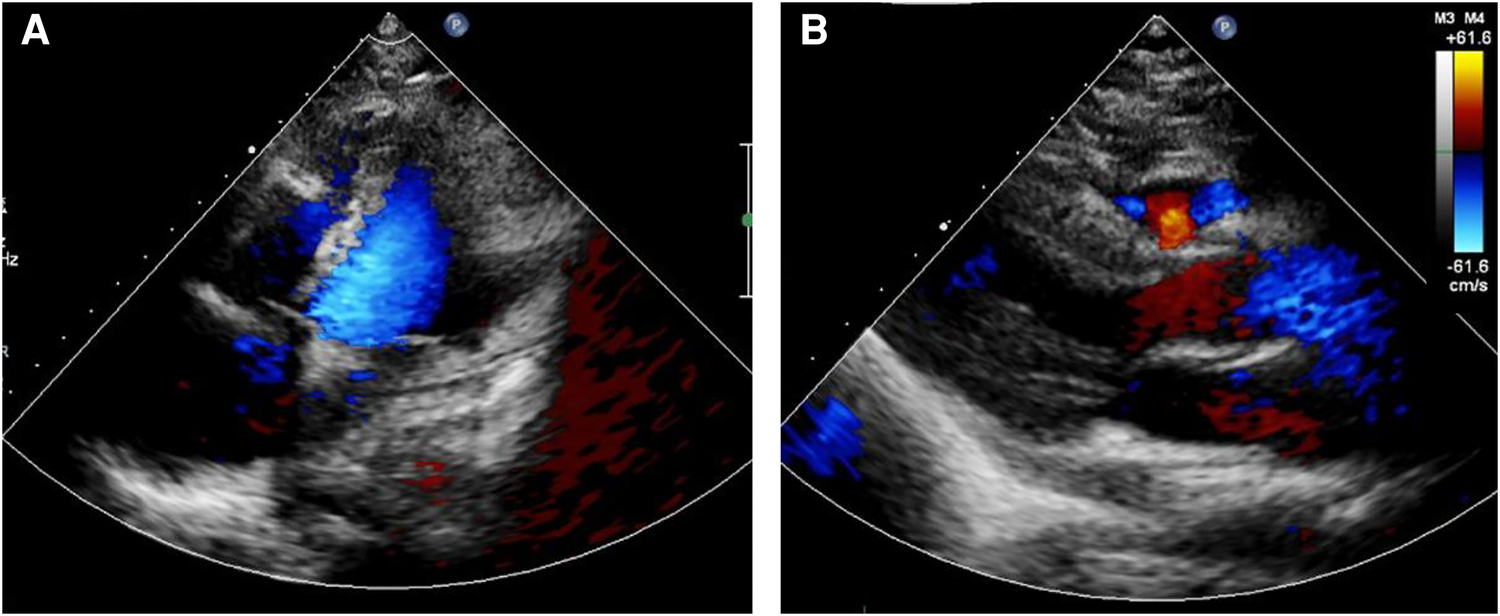

Following the comprehensive evaluation, immediate surgical resection of the cardiac tumor was performed. A giant mass was observed extent encompassing from the right atrial appendage and the superior vena cava, to the right atrioventricular sulcus, the posterior atrial wall, and approximately 2 cm downward from the inferior vena cava opening (Figure 2A, Supplementary Video S1). A cluster of three masses, totaling about 3 cm in diameter, was found located on the right side of the aorta. Notably, a pale red coloration marked the pericardial fluid. An incision was made in the right atrium, facilitating the removal of the mass and the invaded right atrial wall (Figure 2B, Supplementary Video S1). During surgery, the tumor, a small margin (2 cm–3 cm) of the surrounding healthy tissue was removed. Because the procedure was performed with beating heart, tumor excision was performed with great care to avoid damaging the sinus node and causing complete atrioventricular block. The mass, measuring approximately 5 cm × 5 cm × 4 cm, exhibited parenchymal characteristics, a firm consistency, dark red coloration, and an uneven surface (Figures 2C,D). The right atrium was finally reconstructed using a bovine pericardium patch of matching size. The pathology postoperatively from both the right atrium and para-aorta were detected similar and revealed that the grayish-red solid mass featured a 2.5 cm × 2 cm × 1.5 cm size portion showcasing pronounced cellular heterogeneity, conspicuous nuclear divisions, extensive hemorrhagic necrosis, and abundant blood vessels (Figures 3A,B). Immunohistochemistry findings for the right atrial cardiac adenoma indicated CK (-), S100 (-), TLE1 (-), Ki67 (80%+), P53 (5% weak+, possibly indicative of nonsense mutant type expression), Desmin (-), MyoD1 (-), and Miyogenin (-). Immunophenotypic markers SMA (weak+), CD34 (++), CD31 (++), F8 (++), D2-40 (-), ERG (++), HCAL (-), ER (O), P16 (focal+), and CD10 (-) were documented (Figures 3C,D). Post-surgery, the patient's stay in the intensive care unit spanned 18.5 h and discharge on the 12th day with the recommendation of transferred to the oncology department and subsequently underwent conventional and experimental chemoradiotherapy for angiosarcoma [stereotactic radiotherapy and weekly paclitaxel (80–100 mg/m2) for 6 cycles]. During the ensuing six-month follow-up period, the patient exhibited a favorable recovery trajectory devoid of complications, ultimately experiencing a resumption of normal activities without the recurrence of symptoms. The postoperative echocardiography revealed that the right atrial mass was totally resected, no hemodynamic abnormality and no recurrence signals (Figures 4A,B).

Figure 4

Postoperative echocardiography showed that the right atrial mass was totally resected (A), no hemodynamic abnormality (B) and no recurrence signals.